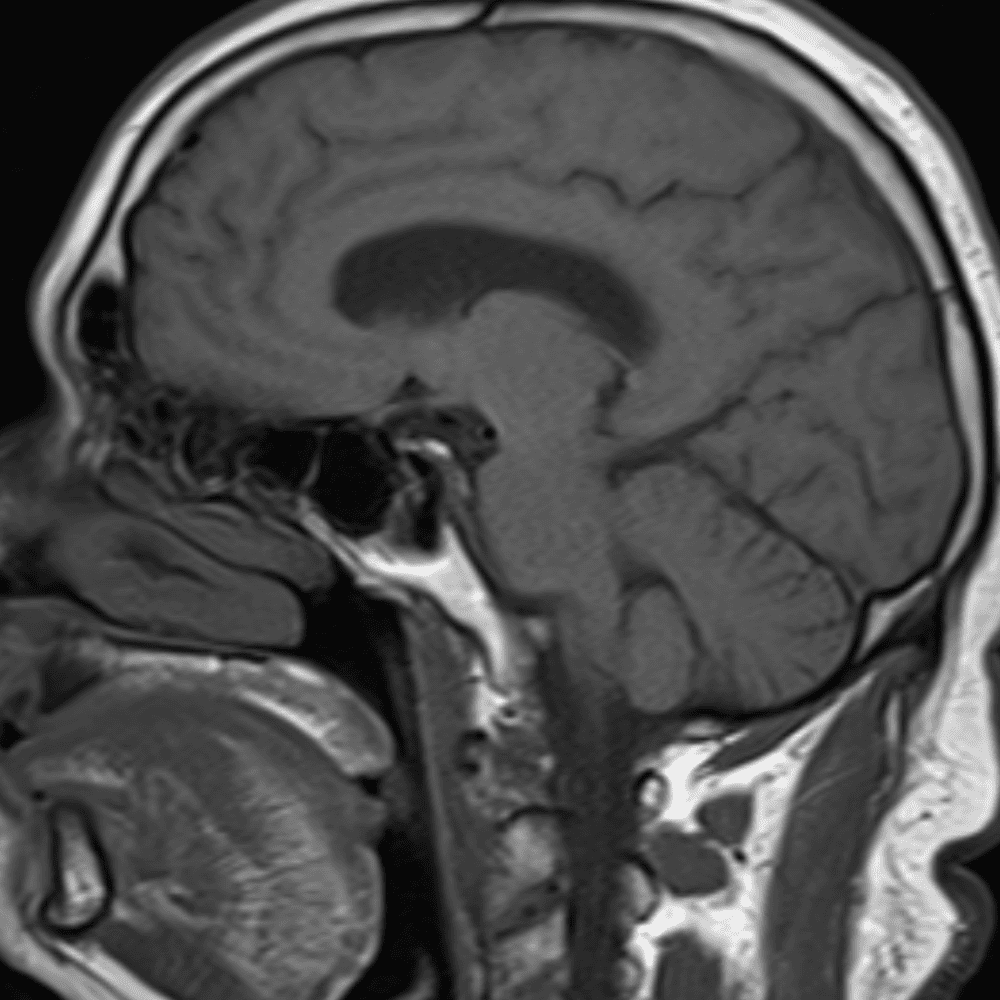

๋‹น์ง ์‹œ ํ”ํžˆ ๋ณผ ์ˆ˜ ์žˆ๋Š” ์‚ฌ๋ก€์˜ ์ „ํ˜•์ ์ธ ์˜ˆ๋ฅผ ํฌํ•จํ•ฉ๋‹ˆ๋‹ค.

39 ์‚ฌ๋ก€

์—ฐ์Šต

๋ฏธ๋ฌ˜ํ•˜๊ฑฐ๋‚˜ ์–ด๋ ค์šด ์‚ฌ๋ก€์™€ ์ผ๋ถ€ ์ •์ƒ ์‚ฌ๋ก€๋ฅผ ํฌํ•จํ•˜์—ฌ ๋‹น์ง์„ ์‹œ๋ฎฌ๋ ˆ์ด์…˜ํ•ฉ๋‹ˆ๋‹ค.

50 ์‚ฌ๋ก€